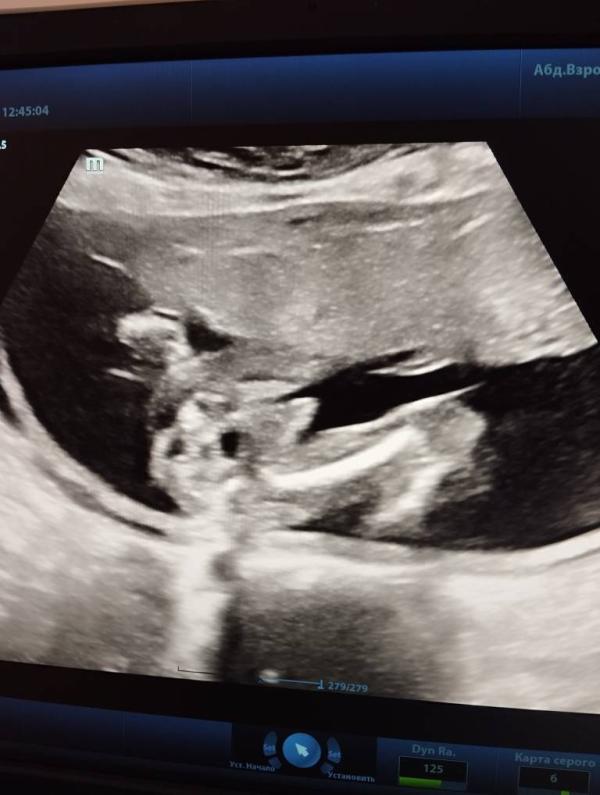

Кто пол определит?

Кто определять пол умеет. Это же мальчик точно,да?🤞🏻💙

Ну там бедра и достоинство между 😁 вроде так)

Мне кажется тут на весь экран хозяйство обозначено 😁

Ну он вам чётко обозначил, что он мужчина 😁